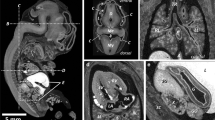

Micro-CT images of two Lugol stained fetuses. a Midsagittal view of 11 weeks gestation fetus, 72 h staining with 3.75% Lugol’s solution result in complete and even staining. b Midsagittal view of 15 weeks gestation, 72-h staining with 3.75% Lugol’s solution result in artifact (star) as result of incomplete staining. Figure adapted from Postmortem microfocus computed tomography for early gestation fetuses: a validation study against conventional autopsy (Hutchinson et al. 2018) [17] with permission from Elsevier (video stills from supplementary data)

All examined publications reported successful scanning of human fetuses with a preclinical UHF-MRI scanner (see Table 2) with a field strength from 7 to 11.7 T. Though the bore diameter of most scanners is between the 16 and 30 cm, the use of a radiofrequency (RF) coil limits the inner diameter of the scanning plane to typically less than 10–20 cm, which hampers scanning whole fetuses > 20 weeks of gestation with these preclinical scanners. Several authors examined the added value of UHF-MRI over low-field MRI [14, 15, 37], as demonstrated in Fig. 5 by Thayyil et al (2009) [14]. They conclude, that UHF-MRI enables scanning on much higher resolution resulting in greater diagnostic usefulness, especially in fetuses below 16 weeks of gestation [14, 15, 37].

UHF-MRI and low-field MRI images of the same fetus. a Coronal, (b) sagittal, and (c) axial images obtained with three-dimensional T2-weighted MRI at 9.4 T. d Coronal, (e) sagittal, and (f) axial images obtained with three-dimensional T2-weighted MRI at 1.5 T. Figure adapted from Post-mortem examination of human fetuses: a comparison of whole-body high-field MRI at 9.4 T with conventional MRI and invasive autopsy (Thayyil et al. 2019) [14] with permission form Elsevier